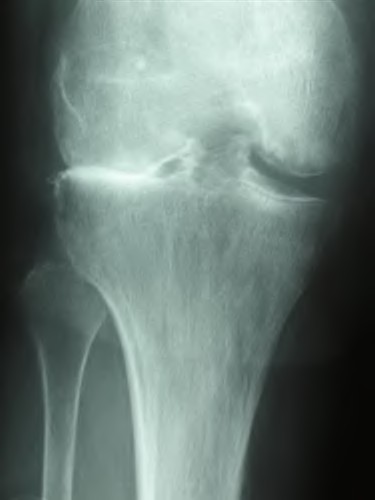

A 65-year-old woman with painful knee arthritis and the deformity seen in Figure A, is scheduled to undergo a total knee arthroplasty. All the following are risk factors for a post-operative peroneal palsy EXCEPT:

The clinical presentation is consistent with end-stage arthritis in a valgus knee. All of the factors listed are risk factors for peroneal nerve palsy EXCEPT female gender, which is not a risk factor.

Peroneal nerve palsy is a potential serious complication of TKA in patients with a pre-operative valgus knee deformity. Peroneal nerve palsy is likely caused by lengthening of the lateral aspect of the knee and subsequent traction on the peroneal nerve. It is generally recommended that patients be evaluated

carefully for symptoms postoperatively. If peroneal nerve palsy symptoms are discovered, the knee should be flexed to relax the tension that is effectively being placed on the nerve. If peri-operative nerve exploration or decompression is undertaken, the posterior border of the biceps-femoris tendon is the proper site of identification.

Idusuyi et al. published a retrospective review of 32 postoperative peroneal nerve palsies in thirty patients in which they identified possible risk factors. Prior proximal tibial osteotomy, lumbar laminectomy (thought to be a “double-crush” phenomenon), and preoperative valgus alignment of 12 degrees or more were all identified as risk factors. Other concerns included epidural anesthesia for postop pain control, preoperative flexion contractures and tourniquette time greater than 120 minutes also increased concern.

Favorito et al reviewed valgus total knee arthroplasty and reported that the most common complications of patients with a valgus deformity include: tibiofemoral instability (2% to 70%), recurrent valgus deformity (4% to 38%), postoperative motion deficits requiring manipulation (1% to 20%), wound problems (4% to 13%), patellar stress fracture or osteonecrosis (1% to 12%), patellar tracking problems (2% to 10%), and peroneal nerve palsy (3% to 4%).

Figure A demonstrates and AP radiograph of the knee showing end-stage arthritis with severe lateral compartment narrowing.